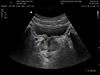

![]() |

Upper abdomen US 상복부 초음파 고해상도 초음파로 간, 담낭, 췌장 등 상복부 장기의 구조와 혈류 상태를 실시간으로 관찰하여 결석, 종양, 염증, 담즙 정체 등 이상을 진단하는 검사입니다. |